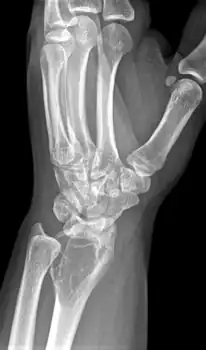

Side view of same wrist

Front view X-ray one-year later it has grown

On X-ray, giant-cell tumors (GCTs) are lytic/lucent lesions that have an epiphyseal location and grow to the articular surface of the involved bone.[11] Radiologically the tumors may show characteristic 'soap bubble' appearance.[12] They are distinguishable from other bony tumors in that GCTs usually have a nonsclerotic and sharply defined border. About 5% of giant-cell tumors metastasize, usually to a lung, which may be benign metastasis,[13] when the diagnosis of giant-cell tumor is suspected, a chest X-ray or computed tomography may be needed. MRI can be used to assess intramedullary and soft tissue extension.